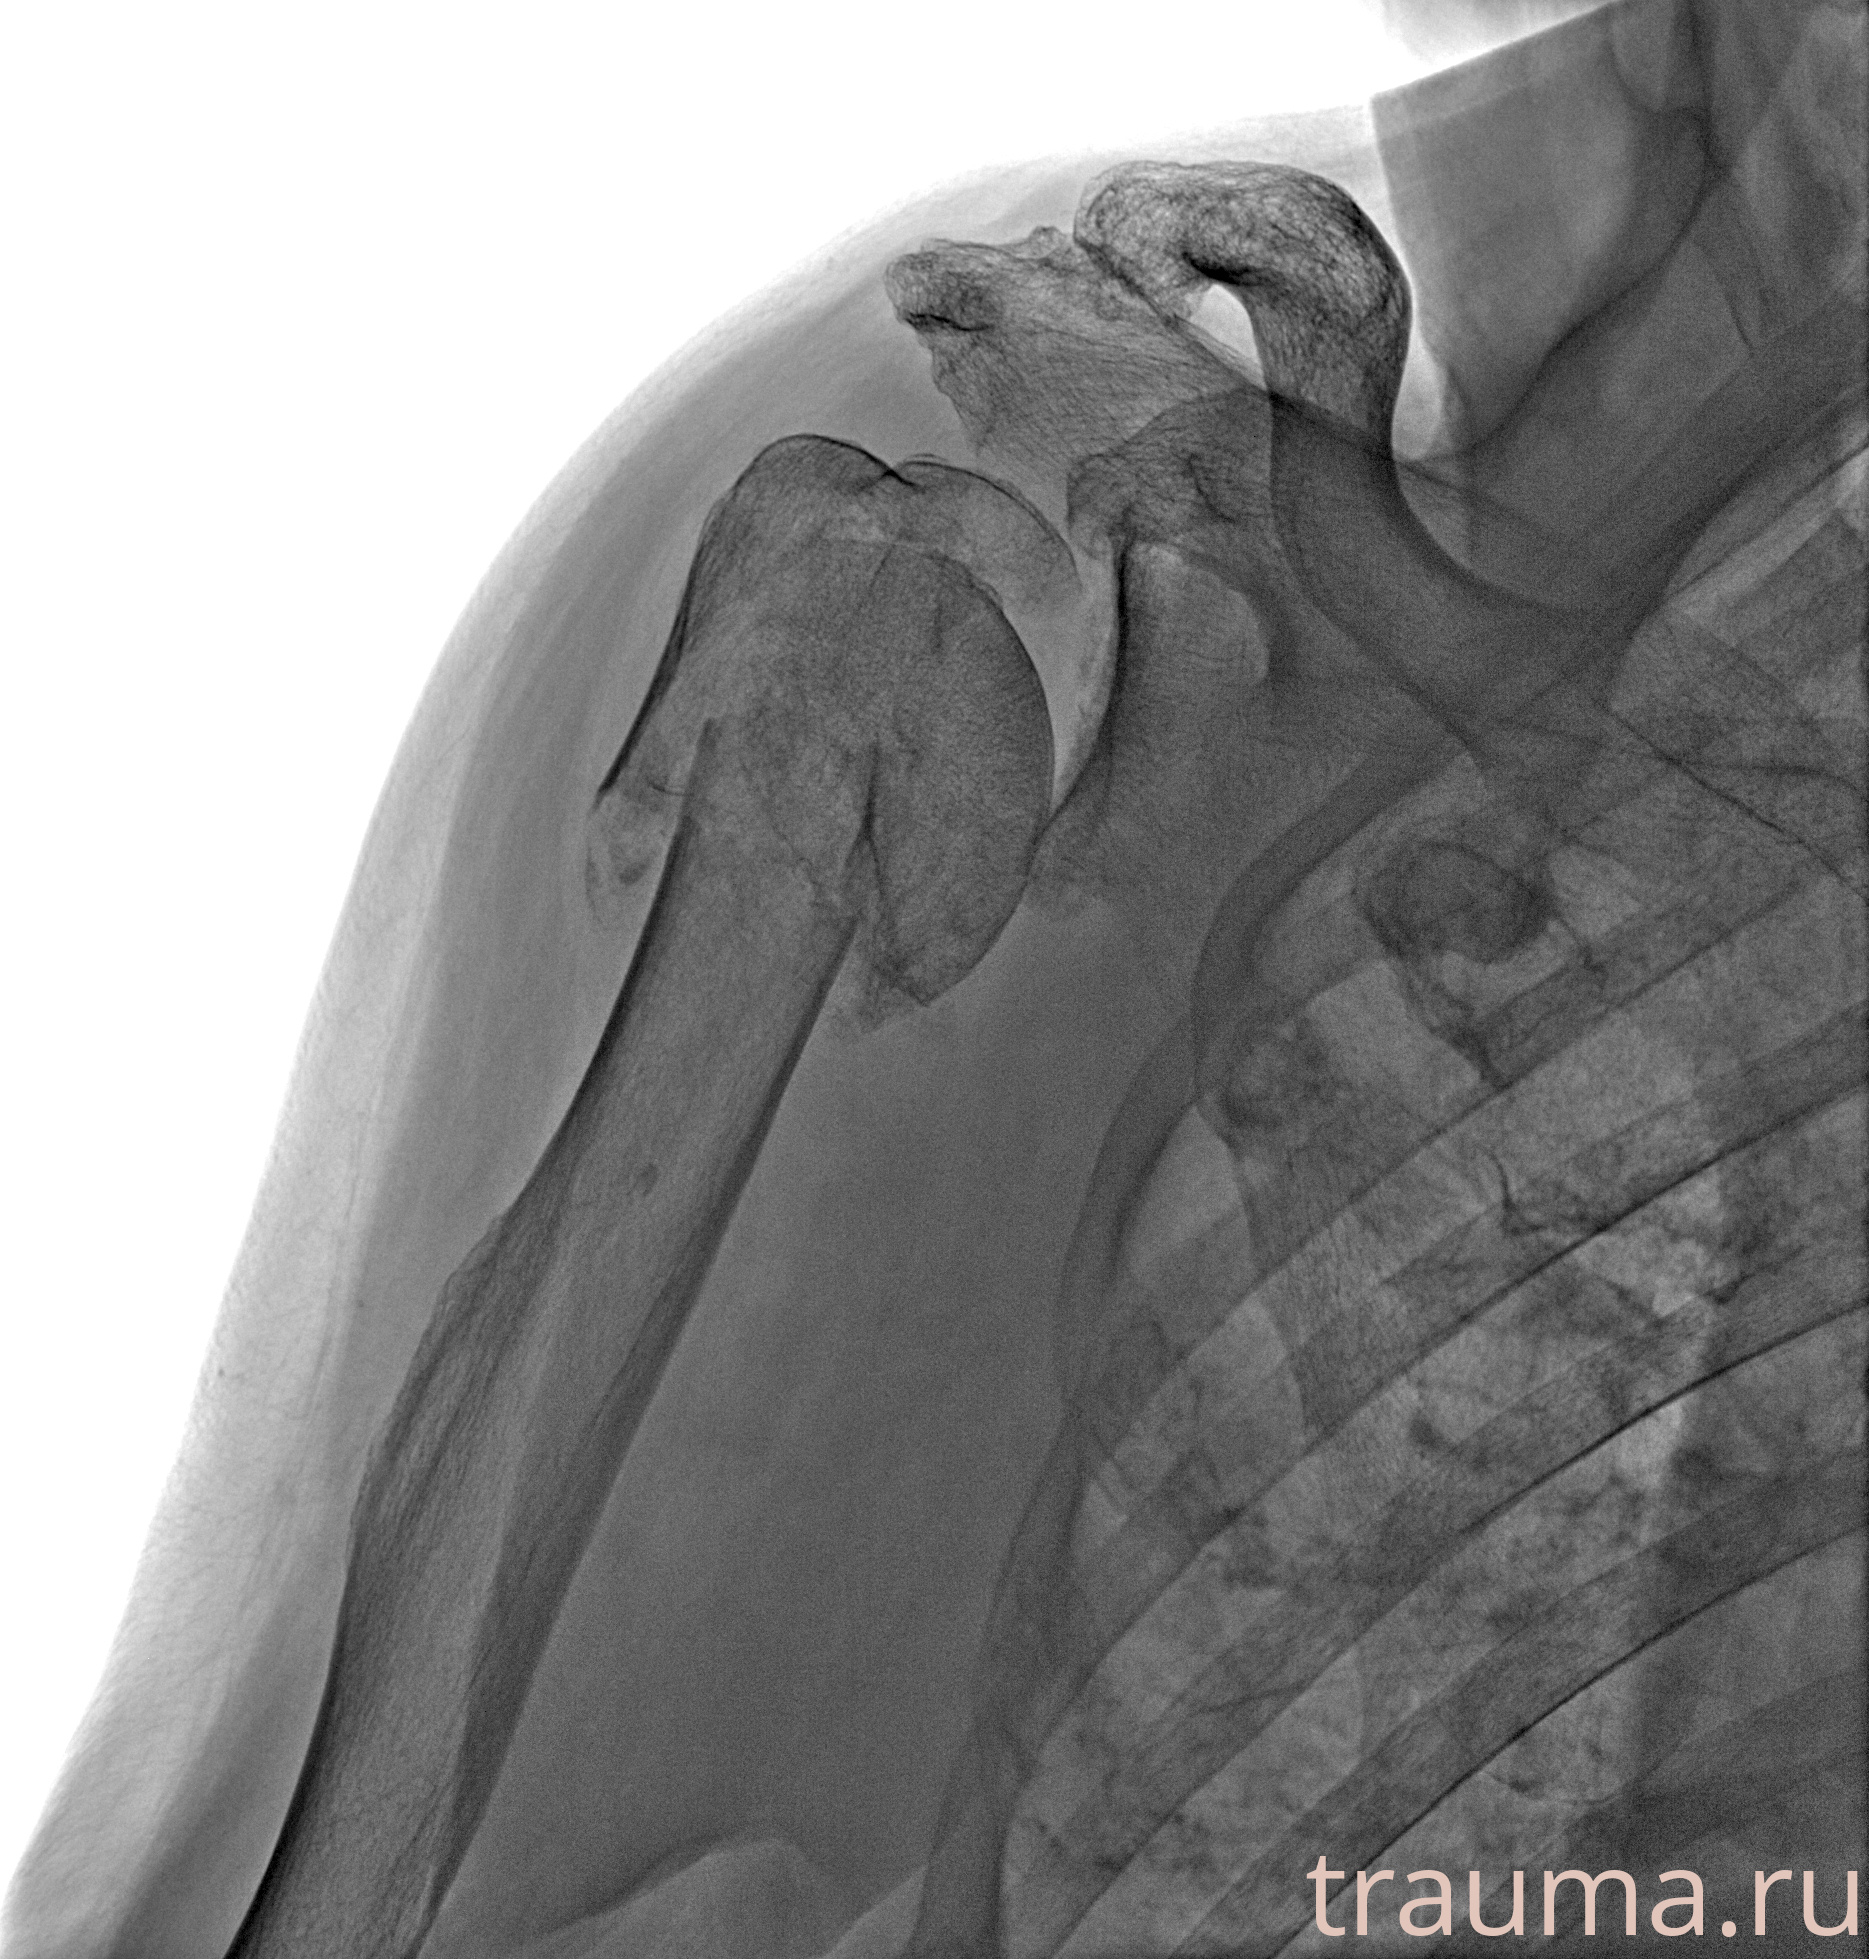

Рентгенограммы

Рентген на дому: по вашему адресу приезжает врач-рентгенолог, травматолог-ортопед с мобильным рентгеновским аппаратом, проводит диагностику травмы или заболевания, делает необходимые рентгенограммы, дает рекомендации по дальнейшему лечению. Получить качественные снимки в домашних условиях возможно благодаря уникальной методике, разработанной МосРентген Центром для института  Склифосовского